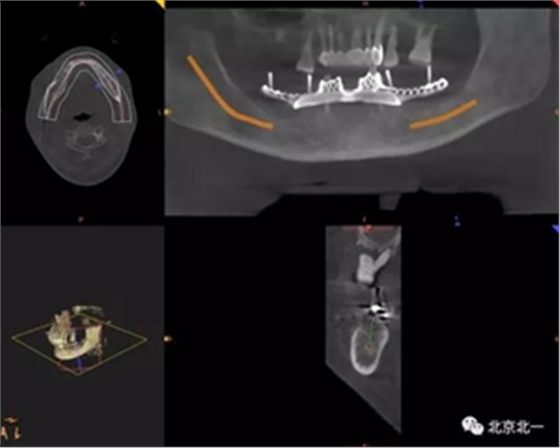

圖一:術(shù)前CBCT

圖二:術(shù)前數(shù)字化設(shè)計種植導(dǎo)航手術(shù),設(shè)計導(dǎo)板

圖二:術(shù)前模擬導(dǎo)板 , 精準植入。